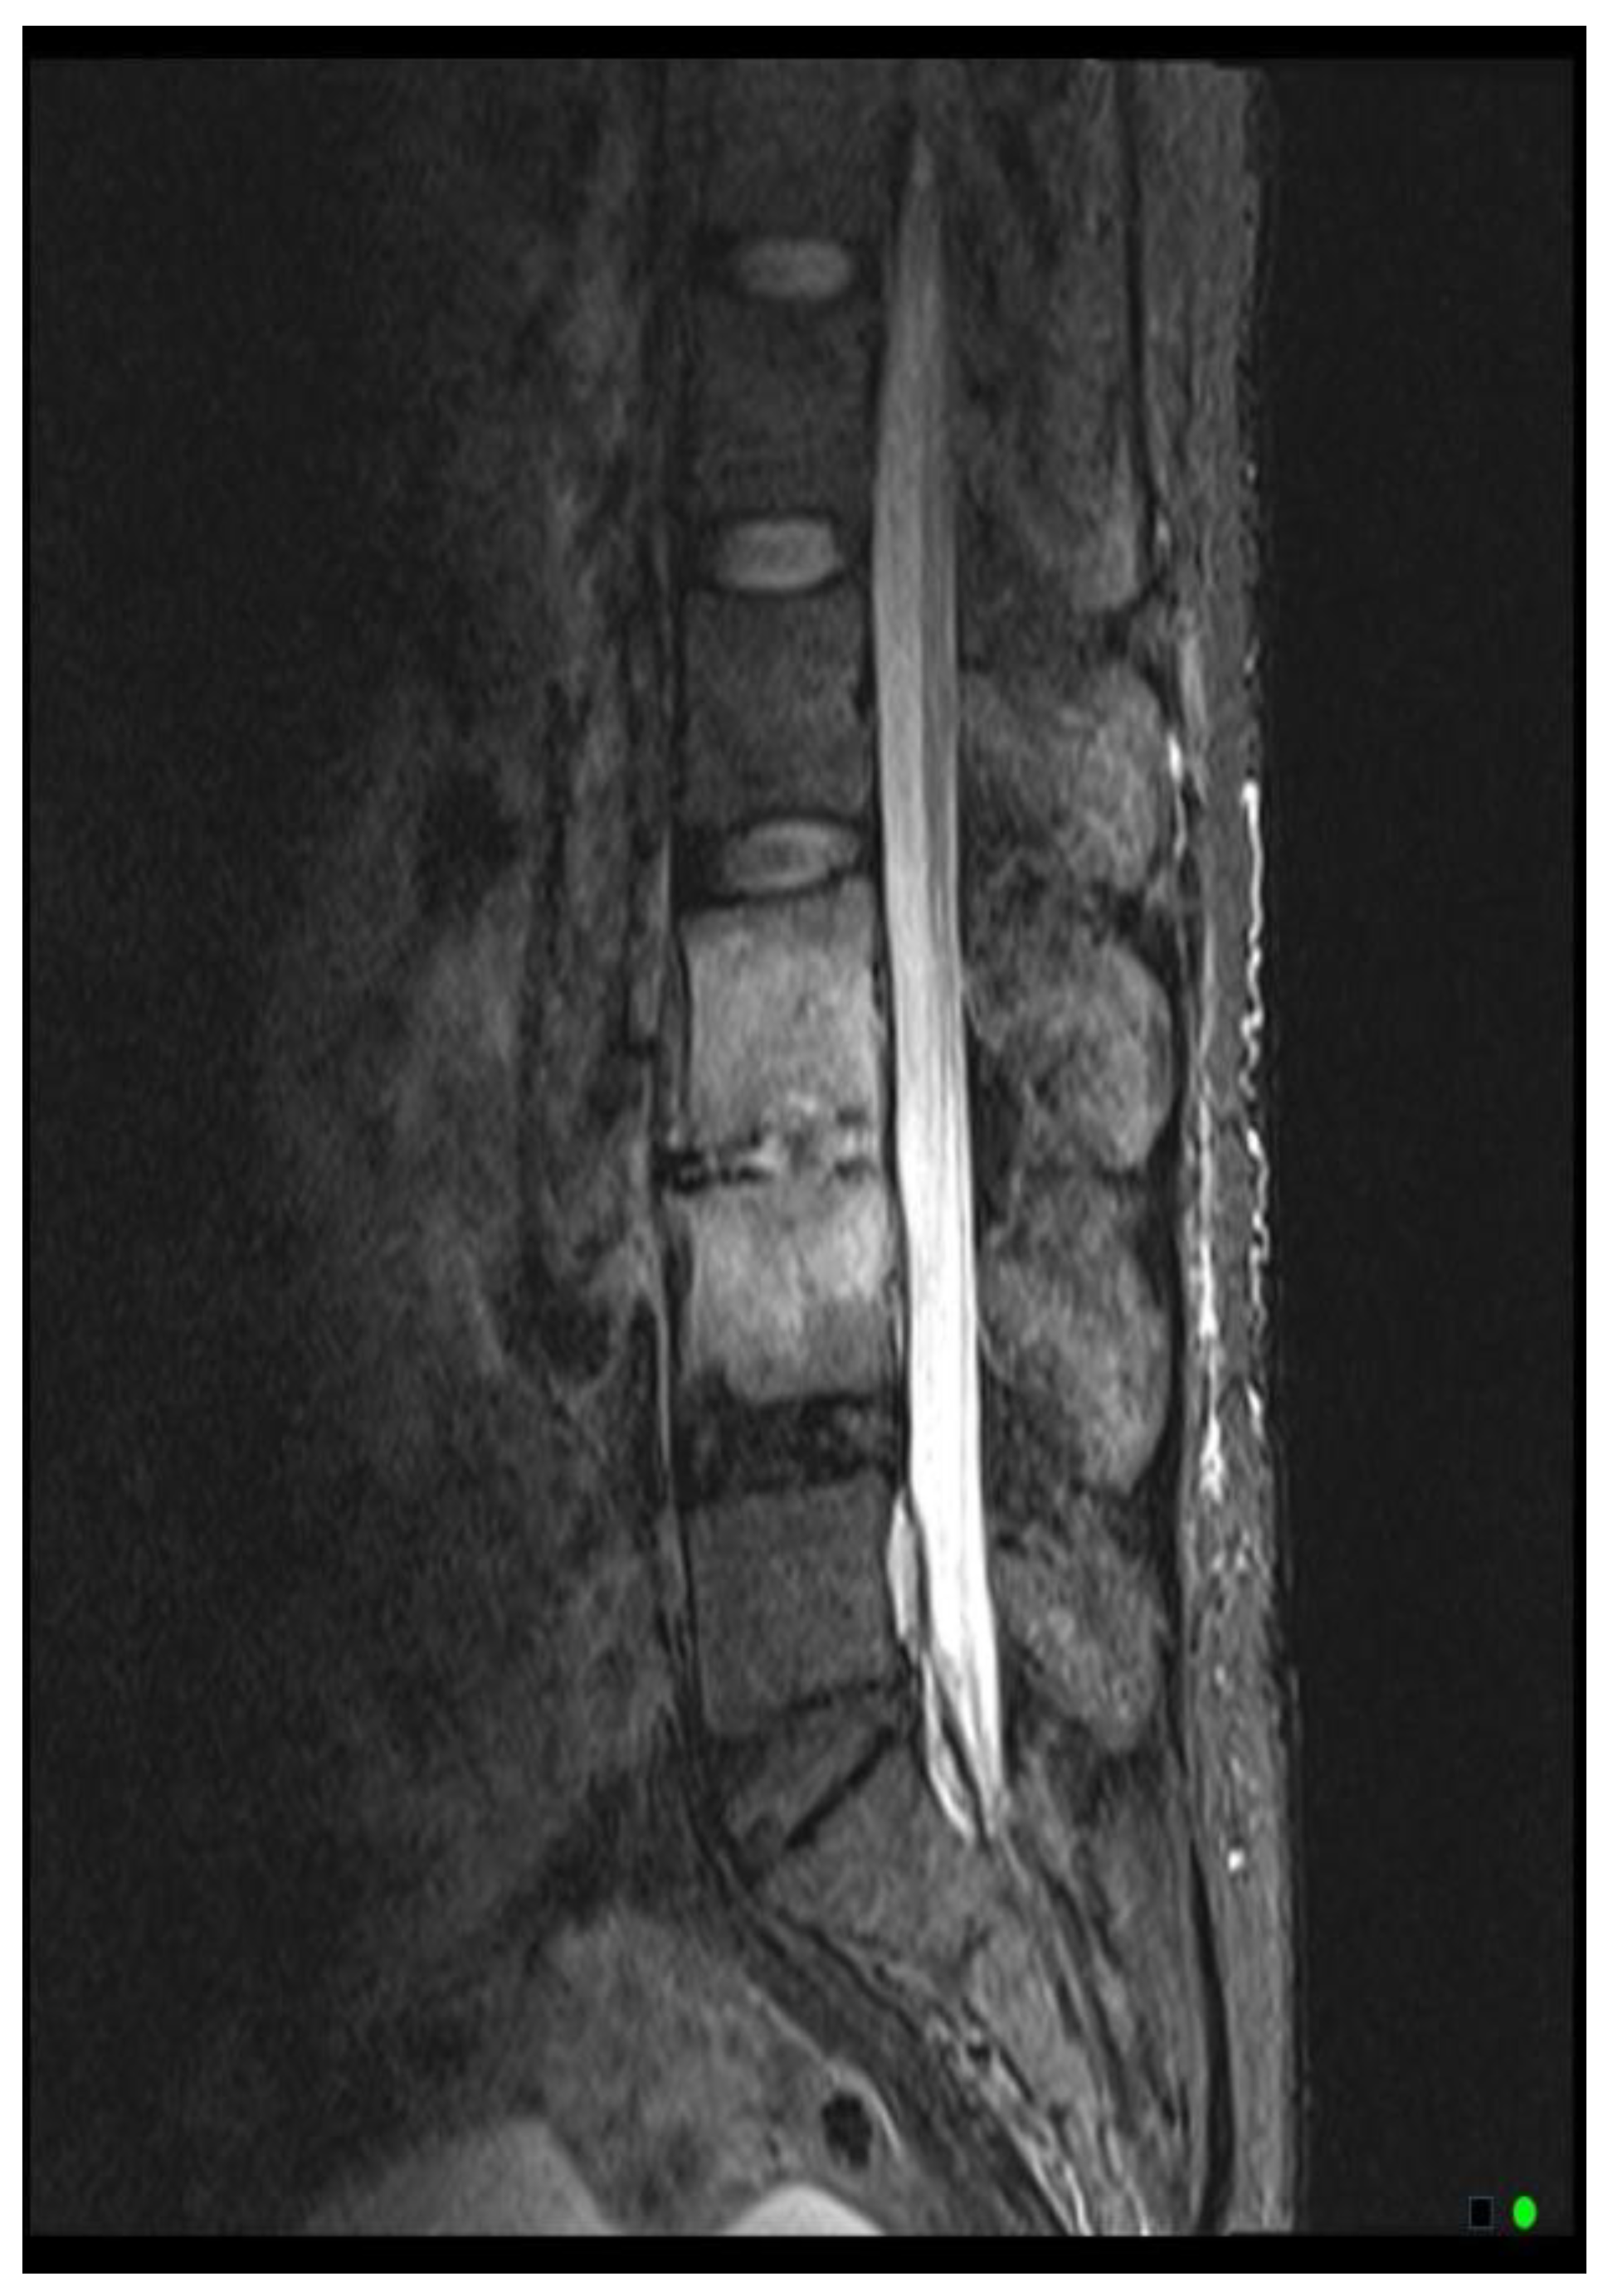

The MRI scoring system utilizes a scale from 1 to 3, with each score representing distinct radiological findings. A score of 1 signifies a hyperintense T2/STIR disc signal, suggesting possible inflammation and edema related to early infection (

Figure 2A). Moving up the scale, a score of 2 denotes both a high disc signal and endplate marrow edema, likely indicative of more advanced stages of VDO (

Figure 2B). Finally, a score of 3 includes high disc signal, endplate marrow edema, and soft tissue edema/abscess, suggesting severe involvement (

Figure 2C).It should be noted that all scoring assessments above were verified using other MRI sequences to improve classification accuracy. For instance, soft tissue edema and abscess can be distinguished from one another using MRI with IV contrast (5). However, differentiating edema from abscess was not necessary for the scope of this study because the presence of either entity could be interpreted as more severe imaging findings related to VDO. Also, as some patients had no MRI with contrast before the biopsy, this approach enabled us to include more patients in our study and simplify the scoring system for greater usability. Thus, we included both soft tissue edema and abscess in the same category, denoted by a score of 3.